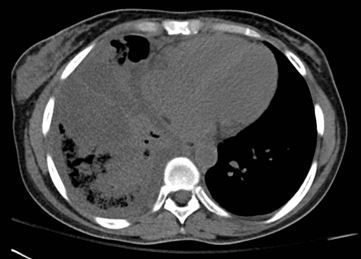

An radiograph of the chest was obtained (Figure 1, top) followed by a CT scan of the chest. A representative axial CT image is shown in Figure 2 (bottom). (Click on figures to enlarge.)